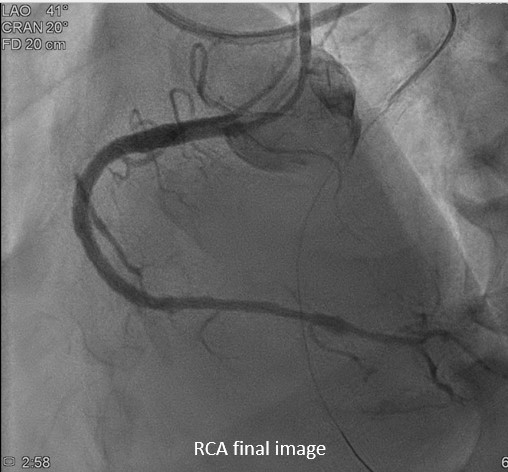

During the staged PCI, antegrade approach with escalating guidewires ended up in subintimal space; retrograde approach from the first LAD-septal branch failed because there was difficulty crossing the existing mid-LAD stent. Further attempts from the third septal branch successfully reached the distal cap of the CTO via proximal descending artery, finally entering the antegrade guide extension catheter by rendezvous technique. After wire externalization and POBA for RCA, the patient became agitated from acute angina, diaphoresis and hypotension. Angiogram of LAD found an acute de novo LAD lesion adjacent to the distal stent edge, leaving only TIMI-1 flow. We stopped the RCA procedure and wired LAD, performed POBA at the de novo LAD lesion and restored coronary blood flow. Then we continued PCI of RCA with POBA followed by the deployment of two DES. Final angiogram showed adequate stent expansion and TIMI-3 flow in RCA. The patient was discharged with no further complications. Follow-up echocardiogram three months later showed improved wall motion and ejection fraction, indicating good myocardial recovery.